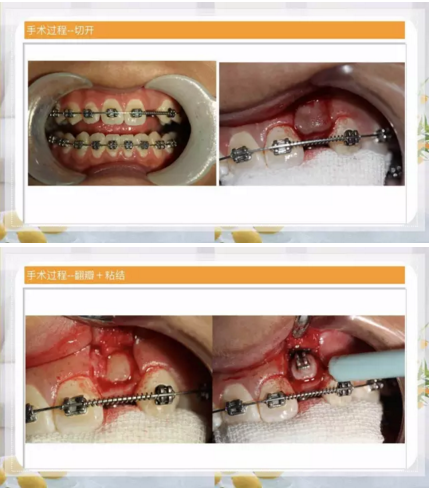

來(lái)源:小白兔口腔鄭穎春

此文關(guān)鍵字:自鎖正畸托槽